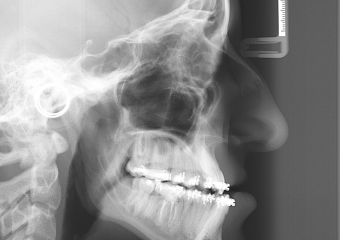

Telerradiografia perfil inicial - Clínica Cliniface

Telerradiografia perfil inicial